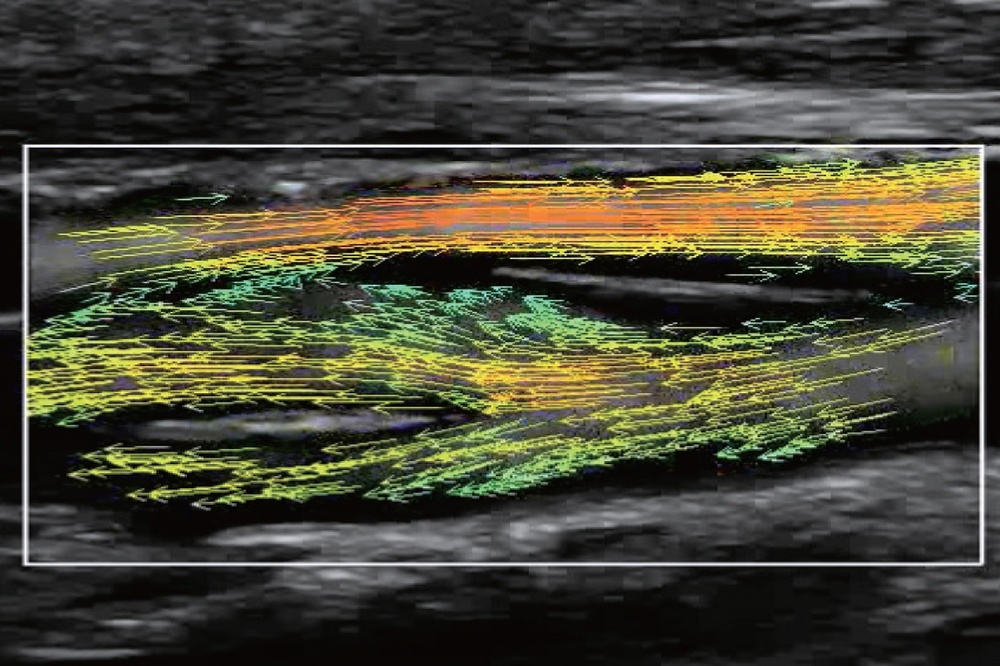

На изображениях, приведенных ниже показаны примеры из клинической практики врачей ультразвуковой диагностики, полученные в процессе апробирования прибора Mindray Resona 7. Приводится наглядные примеры сравнения традиционного режима ЦДК и режима V Flow (Vector Flow).

Изображена яремная вена и бифуркация сонной артерии. CAA, ICA и ECA показаны на одном изображении. В режиме ЦДК отсутствует подробная гемодинамика. В режиме V Flow отображаются данные о скорости и направлении движения частиц крови во всей зоны интереса, включая изменения характеристик кровотока в сонной артерии и яремной вене.